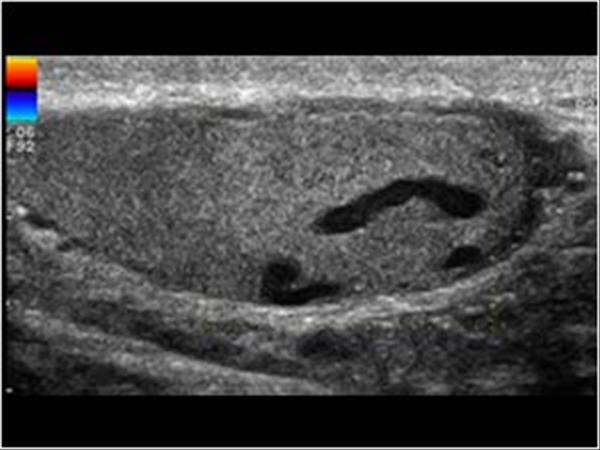

Varicocele